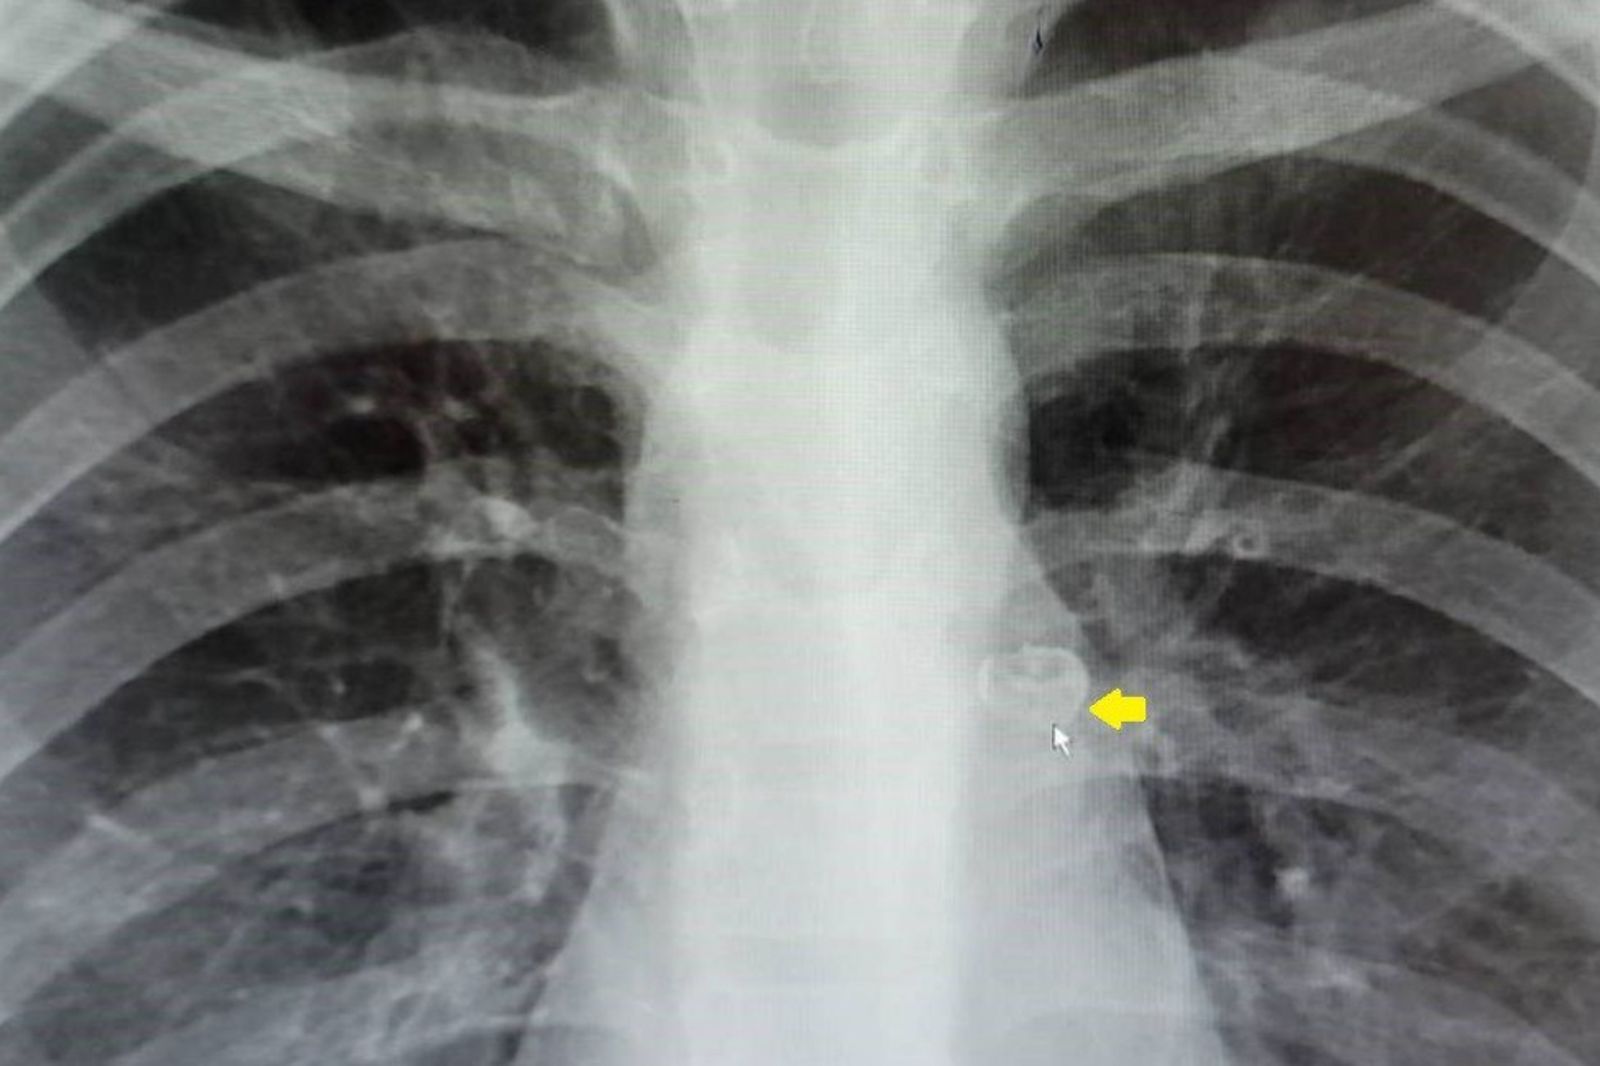

這位小朋友在家人嘗試拔牙後,牙齒竟不翼而飛。家人以為應該是吞下去,會隨排泄物排出,但隔天孩子持續咳嗽,才趕緊送醫。急診拍X光一看,發現牙齒居然卡在左側支氣管裡。醫師立刻安排支氣管鏡手術,才順利把牙齒取出,避免了感染和更嚴重的併發症。